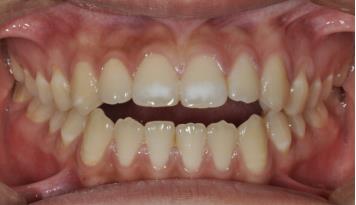

3. 前牙深覆合深覆盖

前牙深覆合是指上前牙覆盖下前牙唇面超过1/3,深覆盖是指上前牙的唇面与下前牙唇面之间的水平距离超过3mm,常常伴有下颌后缩,侧貌呈现凸面型。

矫治方法:前牙深覆合深覆盖的患儿常常伴有吮指,咬下唇,口呼吸等不良习惯,同样,应首先纠正其不良习惯,必要时可在其手指上涂抹苦瓜汁或是辅助矫治装置如唇挡丝、前庭盾等。同时早期可进行肌功能训练,如上唇肌张力训练。口呼吸习惯应进行耳鼻喉科会诊处理,检查其是否伴有鼻咽部疾病,排除鼻咽部疾病后,再使用前庭盾、闭口贴等纠正。针对功能性的因素,常用的矫治器为肌激动器,TB、FRⅡ。针对骨性的因素,常用的矫治器为头帽-肌激动器。